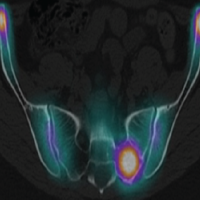

Given the multifocal vertebral and visceral lesions, a systemic primary was suspected, prompting staging with whole-body FDG PET-CT. A baseline whole-body 18F-fluorodeoxyglucose (FDG) positron emission tomography (PET)-CT confirmed a metabolically active pancreatic tail mass measuring approximately 7.8 × 6.4 cm (SUVmax 8.9), with encasement of the splenic vein and involvement of the adjacent splenic parenchyma. Multiple FDG-avid retroperitoneal and peripancreatic nodes (largest 2.0 × 1.8 cm, SUVmax 6.9) and a segment IV hepatic lesion (SUVmax 5.2) were noted. Numerous sclerotic, FDG-avid osseous metastases involved the dorsolumbar spine, sacrum, pelvis, ribs, bilateral femora, and left scapula. An additional soft-tissue lesion at the left lateral aspect of D2 (SUVmax 7.2) showed mild intraspinal extension. Small FDG-avid pulmonary nodules (7 × 4 mm, SUVmax 2.8) were seen bilaterally, consistent with disseminated disease.

A follow-up PET-CT performed 2 months after initiation of chemotherapy showed a partial metabolic response. The pancreatic lesion remained stable in size but demonstrated reduced FDG uptake. Retroperitoneal and peripancreatic lymph nodes decreased in size and activity. The hepatic and marrow lesions showed low-grade residual activity with interval metabolic regression, and the osseous metastases exhibited increasing sclerosis with declining FDG uptake. The previously seen pulmonary nodules had resolved completely.

After 5 months of chemotherapy, repeat PET-CT demonstrated stable disease. The pancreatic primary remained similar in size but showed a mild increase in metabolic activity (>30% SUVmax rise). Retroperitoneal lymph nodes and hepatic lesions showed minor metabolic progression, while skeletal metastases displayed extensive sclerosis and mixed activity. No new lesions were seen. Overall, findings were consistent with morphological stability and mild metabolic progression.

Together, the serial imaging studies demonstrated a metastatic neuroendocrine carcinoma with partial but incomplete response to chemotherapy, showing residual disease in the pancreas, retroperitoneal nodes, and spine, along with interval development of new pelvic metastatic deposits.